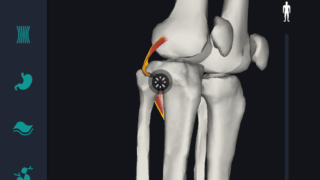

はじめに 本記事では、人体解剖学における専門的な部位の知識を始めに、効果的な勉強法についてご説明します。 人体解剖学では様々な器官や筋肉、骨の名称を覚えるだけではなく、体のどの位置に存在するのかまで覚えなければなりません。そのため、できるだ...